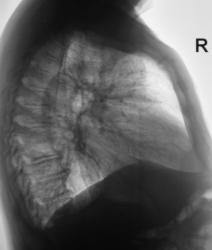

Правосторонний базально-интерлобарный осумкованный плеврит.

При расшифровке флюорограмм пациент был "взят на контроль" с учётом "высокого стояния" и нечеткости контура купола диафрагмы справа. В течении последнего месяца предъявляет жалобы на повышение температуры, боли в грудной клетки справа. Терапевты ничего не слышат. Пациента выявили с учетом "оформления справки" для поступления на работу. Произведено стандартное исследование.

Пришли к выводу о наличии осумкованного базально-интерлобарного плеврита.

В прямой проекции интересно смотрится,  как на локальную релаксацию диафрагмы, но в боковой проекции все понятно сразу.

Все таки, для КТ показания не выражены, достаточно данных линеной томографии. А вот куда он устраивается? Несколько расширена тень сердца и корни за счет легочных артенрий, также имеется "скачок калибра", да и внутрилегочный сосудистый рисунок обогащен, деформирован. Нельзя исключить поражения клапанного аппарата сердца и застоя в малом круге кровообращения. Рекомендовал бы УЗИ сердца.

Уважаемый Валентин Львович! По первому пациенту согласен с Вами, наддиафрагмальный-междолевой плеврит (этиология?). По возможности попытаться достать его ультразвуком, но это мало вероятно если отсутствует контакт жидкости с передней грудной стенкой. Значит остается рентгенконтроль в динамике после курса терапии.